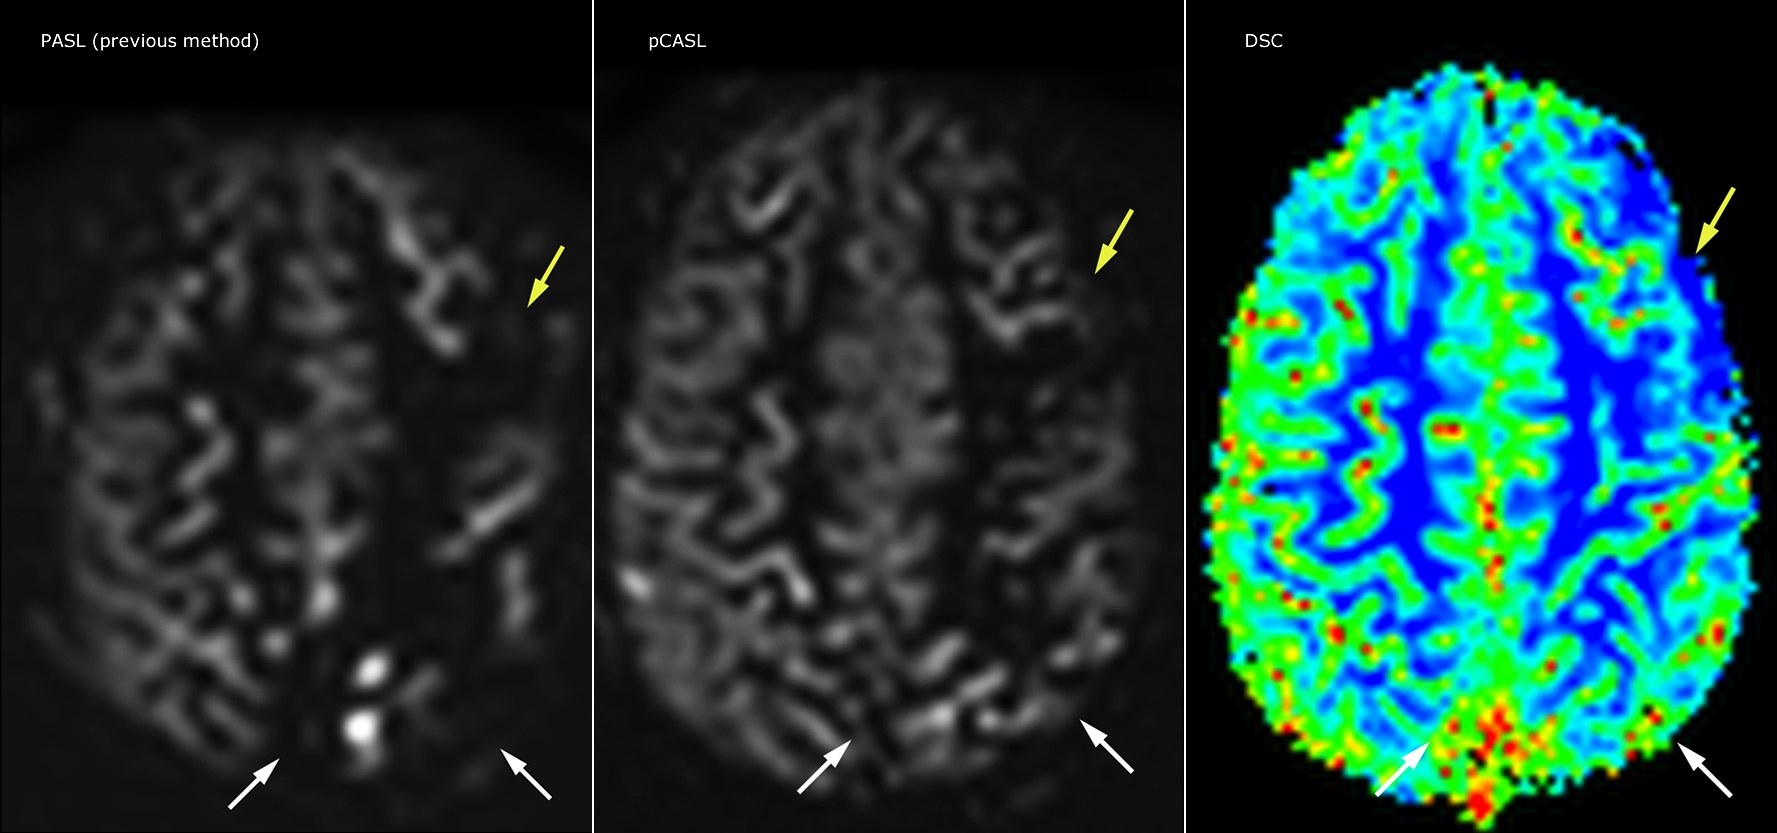

Le marquage des spins artériels pseudo-continu (pCASL) a été développé pour l’imagerie de perfusion cérébrale sans agent de contraste. “C’est vraiment intéressant pour les patients en pédiatrie, où la tendance générale est de limiter l’administration de produits de contraste”, explique le Dr Miller. Accroître la confiance dans des applications spécifiques “Nous avons renforcé notre confiance à l’égard du pCASL en le comparant à l’imagerie de perfusion de contraste. Une fois que nous étions sûrs qu’il représentait ce que les perfusions de contraste représentaient, nous avons amélioré la fiabilité de nos diagnostics par l’imagerie en série de la phase aiguë ou des phases à long terme chez plusieurs patients atteints d’anomalies artérielles.

Le Dr Miller utilise le pCASL pour tous les patients qui se présentent avec des anomalies cérébrovasculaires telles qu’un AVC aigu, ainsi que les patients présentant des signes d’inflammation cérébrale grave, et occasionnellement les patients atteints de tumeurs pour évaluer l’état de perfusion de leurs tumeurs.

“En association avec l’imagerie de diffusion pondérée, il aide à évaluer plus en détail le degré d’anomalie de perfusion chez un patient souffrant d’une ischémie aiguë. Plusieurs de nos patients souffrent d’insuffisance artérielle chronique à cause d’anciennes anomalies artérielles ou d’anomalies artérielles acquises telles que la drépanocytose ou la neurofibromatose. Parfois, la première manifestation de la progression de la maladie chez l’enfant est une réduction dans la perfusion cérébrale avant que les symptômes de l’AVC ne se manifestent cliniquement ou une réduction dans l’imagerie de diffusion pondérée. Nous utilisons le pCASL pour aider à définir l’anomalie de perfusion.”

Je recommanderais également aux autres nouveaux utilisateurs de commencer à interpréter les images pCASL par rapport aux autres images standard, T2, FLAIR et DWI, jusqu’à ce qu’ils puissent interpréter ces images par eux-mêmes en toute confiance.” “L’utilisation du pCASL est efficace chez les patients présentant une sténose cérébrovasculaire chronique, pour laquelle les cliniciens ont besoin d’informations sur la façon dont les mécanismes compensatoires du cerveau fonctionnent pour permettre la perfusion cérébrale. Souvent, les cliniciens prennent en compte la façon dont les mécanismes compensatoires apparaissent pour pouvoir administrer la perfusion adéquate au cerveau du patient. Ils peuvent également intervenir chirurgicalement ou prendre d’autres décisions de prise en charge.” “Une autre application spéciale est l’évaluation de la réactivité cérébrovasculaire avec un examen de perfusion Diamox, lors duquel on soustrait deux ensembles d’images pCASL.”

“Pour nous, désormais, le pCASL est plutôt devenu une acquisition de première ligne pour évaluer la perfusion, par opposition à l’imagerie de perfusion basée sur la DSC avec agent de contraste. Chez les patients qui ne sont pas censés recevoir de produit de contraste, nous pouvons réaliser un pCASL pour l’imagerie de perfusion sans avoir à arrêter l’examen, sortir le patient et poser une IV. Il annule également la nécessité du post-traitement pour les contrastes de susceptibilité dynamiques. En outre, il nous permet de répéter l’imagerie de perfusion sur le même patient et pendant la même imagerie, ce qui nous aide en termes de mouvements du patient, ou lorsqu’une acquisition doit être effectuée avant l’imagerie de perfusion pharmacologique.”